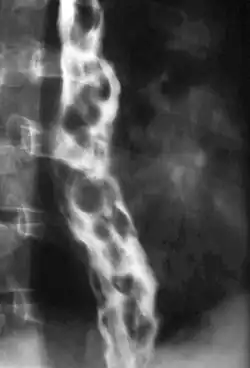

X-ray of a person with dilated, snake-like esophageal varices secondary to pulmonary hypertension

In some circumstances, people with known varices should receive treatment to reduce their risk of bleeding.[6] The non-selective β-blockers (e.g., propranolol, timolol or nadolol) and nitrates (e.g., isosorbide mononitrate (IMN) have been evaluated for secondary prophylaxis. Non-selective β-blockers (but not cardioselective β-blockers like atenolol) are preferred because they decrease both cardiac output by β1 blockade and splanchnic blood flow by blocking vasodilating β2 receptors at splanchnic vasculature. The effectiveness of this treatment has been shown by a number of different studies.[7]

However, non-selective β-blockers do not prevent the formation of esophageal varices.[8]